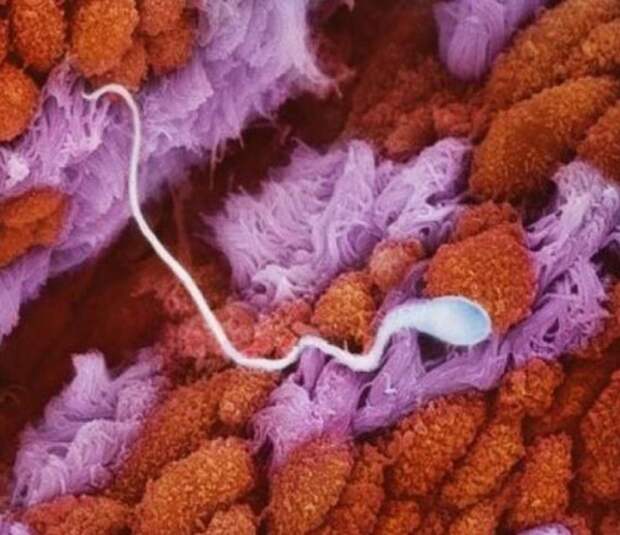

1. Сперматозоид в маточной трубе движется навстречу яйцеклетке.